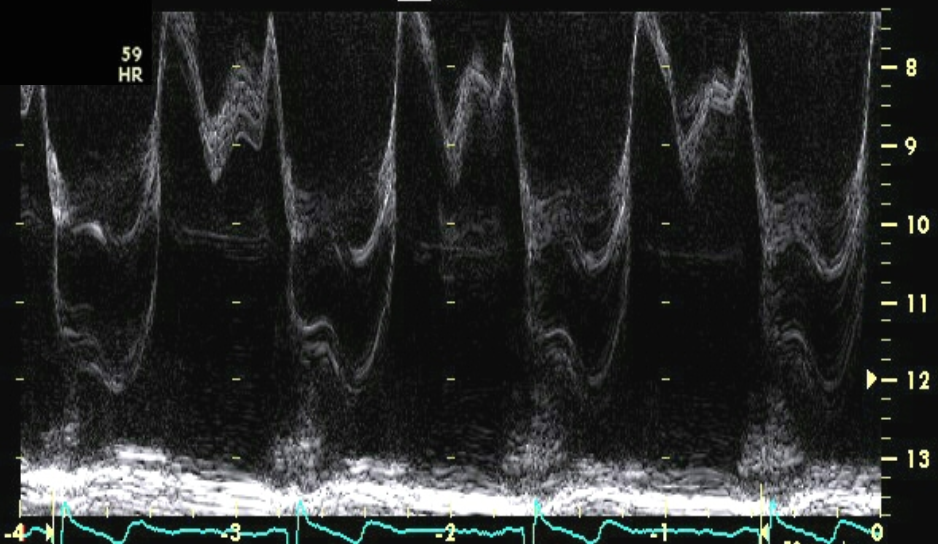

which MR is more severe?

the top one (more dense jet, holosystolic vs. end-systolic only)